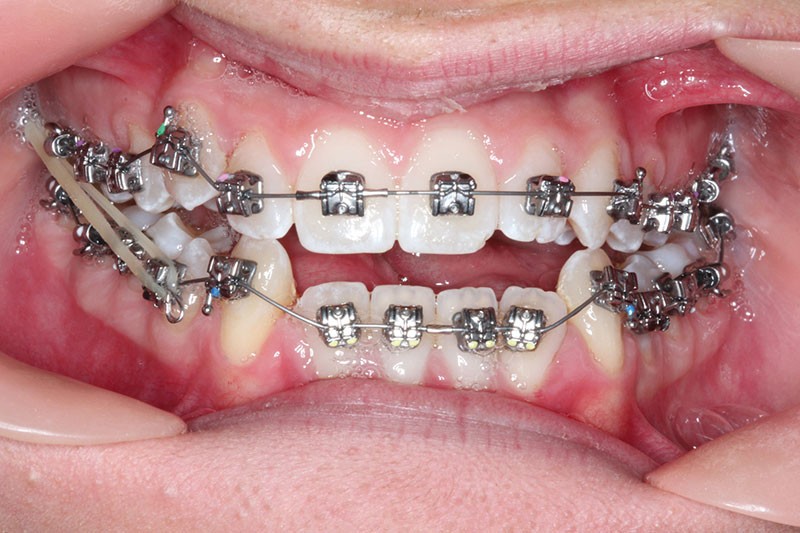

2e phase : mise en place du système multibague Carriere SLX (fig. 7 à 9)

Nous continuons le port des élastiques…